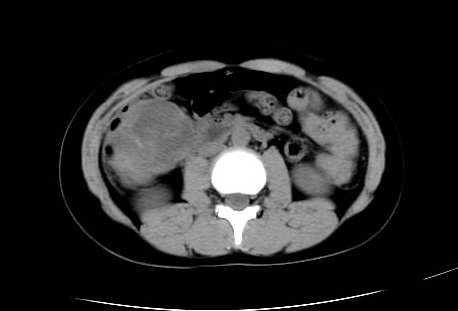

女 16岁  右上腹痛一天,无其他不适

肿块最大径位于十二指肠降段与水平段移行处,并且与肝脏压迹呈“0”形征,可以考虑位于肝外并与胃肠道关系紧密,考虑胃肠道间质瘤(gist)可能较大,须除外神经节起源肿瘤。

肿块与十二指肠关系密切,支持间质瘤诊断.肝脏与结肠均为受压改变.

右下腹巨大肿快,密度不均匀,内见坏死低密度区,边界清楚,与周边胀器明显有分界,未见强化,多考虑来源于间叶组织的良性肿物.

我坚决反对您的观点,该病例定位:横结肠肝曲与升结肠之间的肠系膜及部分肠壁。请看下图:

病灶巨大,少部分向肠腔内生长,大部分向长腔外生长。其密度不均匀,增强显示明显不均匀强化,并见有大片状始终不强化的不规则坏死液化区。虽然病灶中上部形态尚可,病人又如此年轻,但中下部形态、密度、强化特点强烈提示为恶性病灶。综上,我考虑本病例为:恶性胃肠道间质瘤。